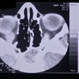

- Linear Nevus Sebaceous Syndrome

- linear nevus sebaceous syndrome, CT scan

- CT scan of linear nevus sebaceous syndrome.